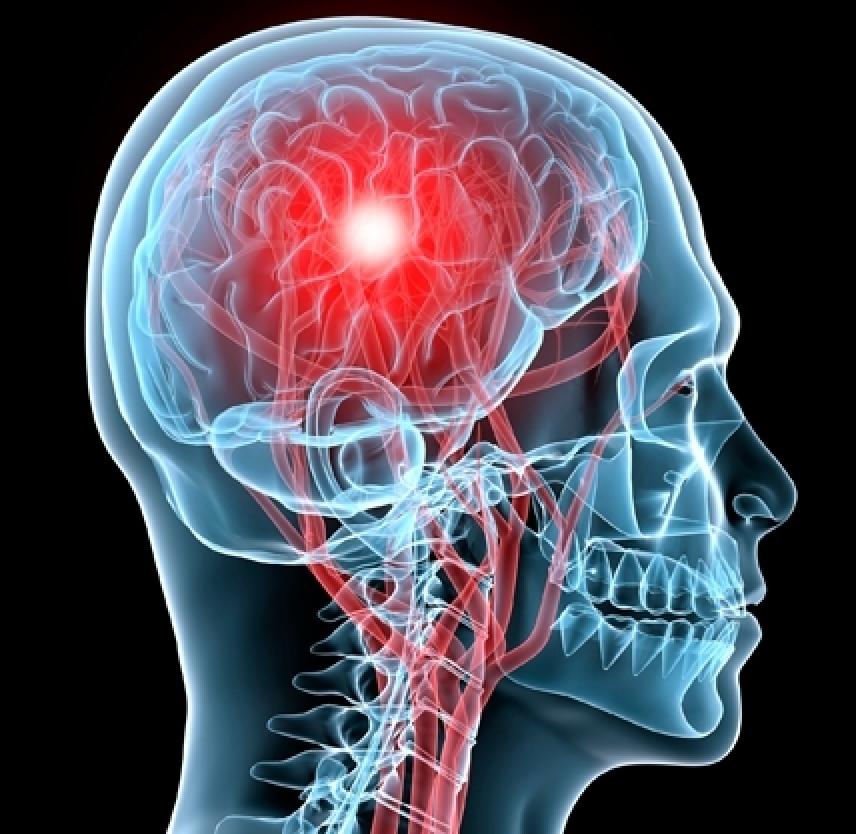

In the past, a blow to the head with potential concussion might have led to the recommendation to avoid sleep for some time. It was thought that if you failed to stay awake you would fall into a coma or lose consciousness. It was also believed that the severity of a head injury should be checked on periodically to see if there was a change in alertness.

Current evidence shows that sleep speeds brain recovery. The first days after a concussion are important to brain recovery. It is encouraged to have physical and mental rest to aid the healing process. Extended bed rest is not recommended because it decreases muscle strength and changes how your body processes energy, along with other harmful effects. After a few days rest, people with a concussion should ease back into their regular activities.